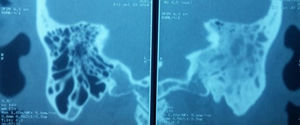

Caso 2Paciente de sexo masculino de 43 años con antecedente de enfermedad renal crónica en tratamiento sustitutivo con hemodiálisis. Se presenta al servicio con aumento de volumen en región retroauricular derecha y otorrea de 15 días de evolución. El estudio de imagen corroboró el diagnóstico de otitis media complicada con absceso de tejidos blandos y petrositis, razón por la cual se le realizó mastoidectomía radical y drenaje del absceso de los tejidos blandos (fig. 2).

En el caso 2 el paciente se presentó con absceso de tejidos blandos y petrositis secundarios a la extensión de la infección de la otitis media siendo esta última una complicación rara y tardía de la otitis media purulenta, sin antecedentes de otorrea con un cuadro agudo. En la TC se observó la mastoides derecha con datos de enfermedad crónica por lo que se trata de una otitis media crónica agudizada. Con relación a la petrositis, cuando la inflamación se extiende en el canal de Dorello, el cual contiene el VI nervio craneal y el ganglio de Gasser, se desarrolla el síndrome de Gradenigo, caracterizado por una tríada de síntomas: parálisis del recto externo (VI nervio craneal), dolor retroorbitario (en la distribución de V nervio craneal) y otorrea4,10. En nuestro caso se encontró el ápex petroso ipsilateral ocupado por material purulento, como la mastoides y la caja timpánica, sin presentar sintomatología orbitaria y/o trigeminal. El factor adicional de riesgo en este paciente fue la insuficiencia renal crónica.